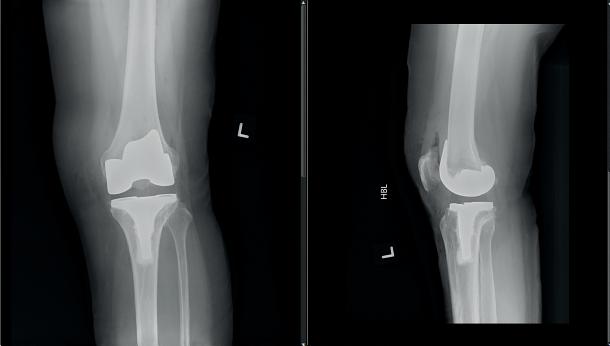

Knee pain is one of the most common joint complaints that can significantly impact daily activities and quality of life. Understand its causes and available treatments so you can take steps toward better knee health and mobility!

In consultation with Dr Sim Wei Ping, Consultant, Orthopaedic Surgery, KTPH

Osteoarthritis is the most common cause of chronic knee pain. This occurs when the protective cartilage in the knee joint gradually wears down. This condition often develops with age, but can also be influenced by body weight, previous injuries, and genetics. The breakdown of joint cartilage and underlying bone changes leads to inflammation, causing pain and stiffness.

Surgical options: When conservative treatments become inadequate, your doctor may recommend surgical options like a knee replacement. This can significantly improve quality of life. Surgery has been shown to:

The most common surgical option is a Total Knee Replacement. This involves replacing the whole knee joint with prosthetic components made of surgical-grade metal alloys and plastic. It is typically recommended for

patients with widespread knee damage. As an alternative, Partial (Half) Knee Replacement is suitable for people whose knees only have partial damage. This less invasive option preserves more of the natural knee tissue and allows a faster recovery time. This surgery has a smaller incision, involves less blood loss, and provides a more natural knee movement.

Modern knee replacements are built to last; though longevity varies on factors like physical condition, activity level, and body weight. With modern advances in surgical technology, knee replacement surgery is more precise than ever before. This will allow surgeons to restore your knee to as close to its pre-disease state as possible, thereby improving function and satisfaction.

Our knee replacement journey has significantly improved over the years. Prior to surgery, we provide comprehensive classes to ensure you are fully prepared. Thanks to our enhanced recovery protocols, you can look forward to walking soon after the procedure, supported by our dedicated therapy teams. We believe in personalised solutions because everyone is unique. Our approach is to tailor the techniques to meet your specific needs. Scan this QR code to find out more!